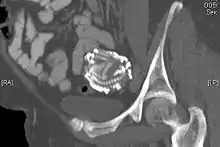

An 80-year-old woman presented in the outpatient department with severe abdominal pain. Ultrasound examination revealed a large echogenic mass (20 x 20 cm) in the right upper quadrant. An abdominal x-ray demonstrated the skeleton of a fully developed extrauterine fetus. It is presumed from the patient's history that this fetus was present for at least 40 years. Radiography revealed a fetus shrouded in a mantle of calcification. The fetus was hyper-flexed with other signs of "intrauterine" death. Fetal dentition charts dated the fetus at 34 weeks, the epiphyses being obscured by extensive calcification. In addition to subcutaneous calcification there was extensive visceral and intracranial calcification.[24] |